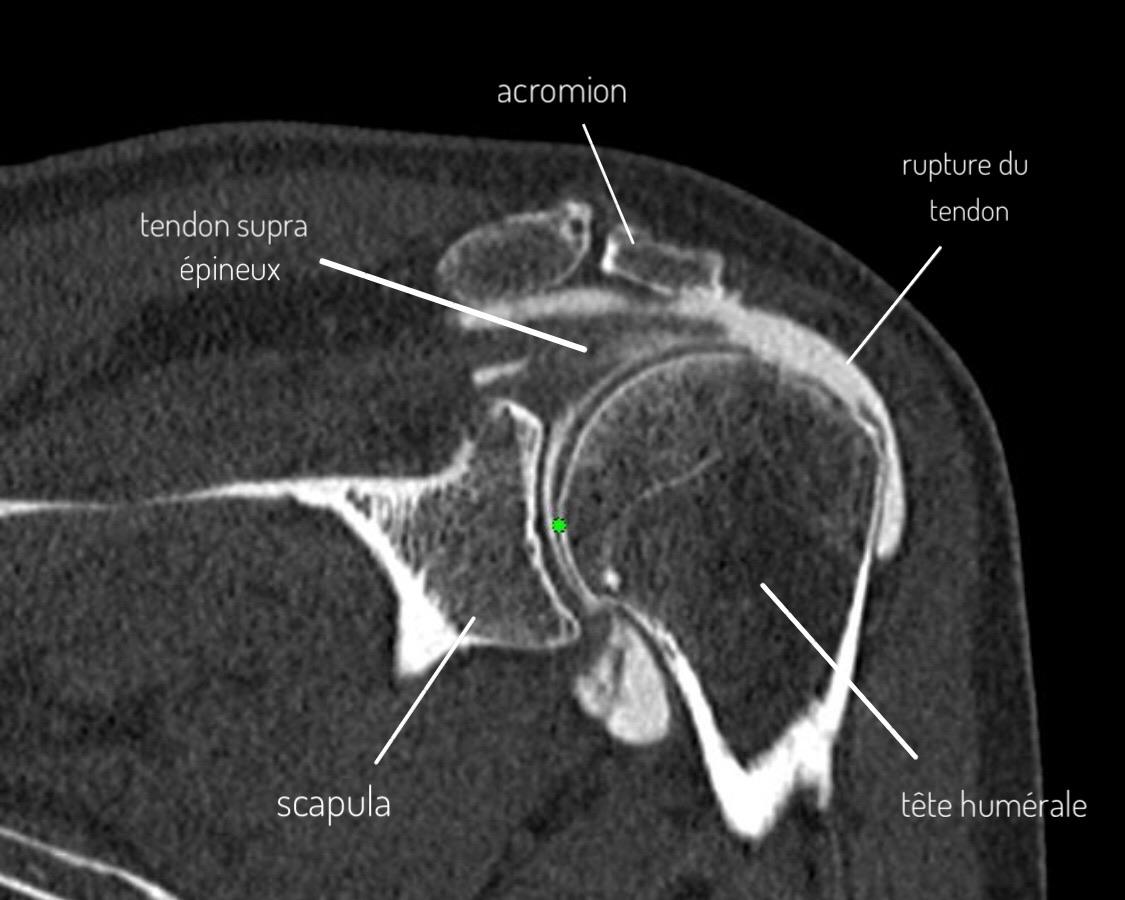

Arthro-MRI or arthro-CT: reference examination

This is the Gold Standard to confirm and assess a rotator cuff lesion, particularly in the context of preoperative assessment.

During this examination, a contrast agent injection is performed in the shoulder joint (between the humeral head and the scapula), followed by a CT scan or MRI.

The distribution of the contrast agent in the joint will allow perfect visualization of the different rotator cuff tendons as well as bone, cartilaginous and ligament structures.

This examination will therefore allow visualization of possible fissure or complete or incomplete rotator cuff rupture, consequence of prolonged subacromial impingement or fall.

It allows in particular:

• Precise visualization of the affected tendon(s) (supraspinatus/infraspinatus, subscapularis)

• Evaluation of lesion size (length and width)

• Evaluation of transfixing or non-transfixing character (affecting the entire tendon thickness or only partial)

• Evaluation of tendon retraction (stage 1, 2 or 3)

• Evaluation of muscle atrophy as well as fatty involution of muscle bodies (stage 0 to 4)

All these elements will allow defining the patient's operability criteria, particularly the technical possibility of reinserting the tendon in good position but also by muscle state to evaluate the subsequent functional character of the repair.

Arthro-CT showing supraspinatus tendon rupture

Arthro-CT: Supraspinatus tendon rupture